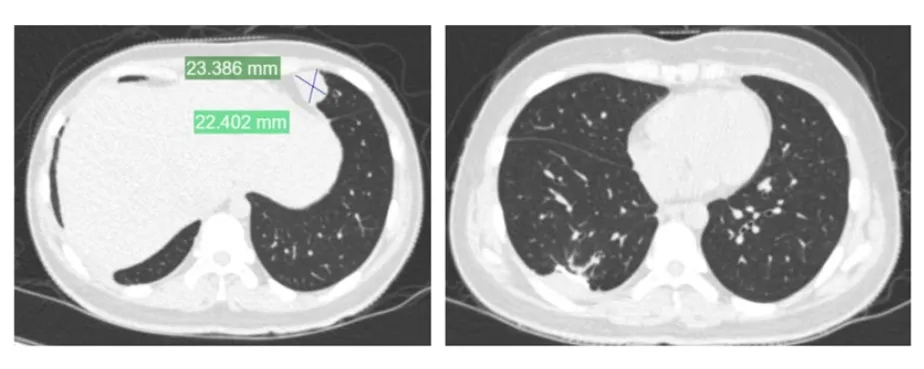

安徽合肥23歲女孩「夏夏」,18歲確診骨癌、19歲截肢,撐過6次重大手術,5年來一路與癌症對抗。她近日再度傳出癌細胞轉移至肋骨與胸膜,需展開新一輪治療。

夏夏因癌細胞轉移,在網上公布要切除肋骨和胸骨。

夏夏複查查出癌症轉移到肺部。

然而,病情並未就此結束。今年初(2026年),夏夏再度檢查出癌細胞轉移至肋骨與胸膜,目前正在上海瑞金醫院評估治療方案,預計接受新一輪化療、標靶治療及手術。